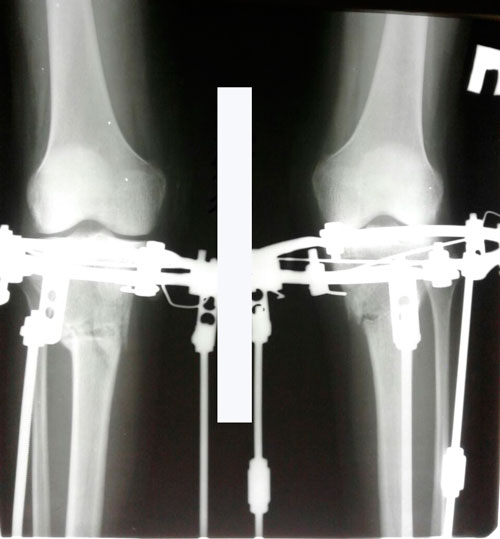

Исходник - 24 года.

2-я ротация.

Дата операции 19.07.2017г.

Дата операции 19.07.2017г

Дата снятия аппаратов 17.10.2017г.

Срок лечения 88 дней.